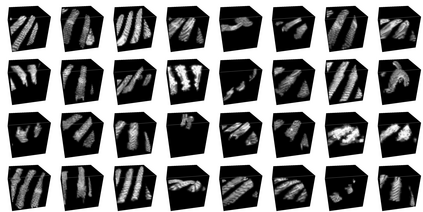

Rib fractures are a common and potentially severe injury that can be challenging and labor-intensive to detect in CT scans. While there have been efforts to address this field, the lack of large-scale annotated datasets and evaluation benchmarks has hindered the development and validation of deep learning algorithms. To address this issue, the RibFrac Challenge was introduced, providing a benchmark dataset of over 5,000 rib fractures from 660 CT scans, with voxel-level instance mask annotations and diagnosis labels for four clinical categories (buckle, nondisplaced, displaced, or segmental). The challenge includes two tracks: a detection (instance segmentation) track evaluated by an FROC-style metric and a classification track evaluated by an F1-style metric. During the MICCAI 2020 challenge period, 243 results were evaluated, and seven teams were invited to participate in the challenge summary. The analysis revealed that several top rib fracture detection solutions achieved performance comparable or even better than human experts. Nevertheless, the current rib fracture classification solutions are hardly clinically applicable, which can be an interesting area in the future. As an active benchmark and research resource, the data and online evaluation of the RibFrac Challenge are available at the challenge website. As an independent contribution, we have also extended our previous internal baseline by incorporating recent advancements in large-scale pretrained networks and point-based rib segmentation techniques. The resulting FracNet+ demonstrates competitive performance in rib fracture detection, which lays a foundation for further research and development in AI-assisted rib fracture detection and diagnosis.